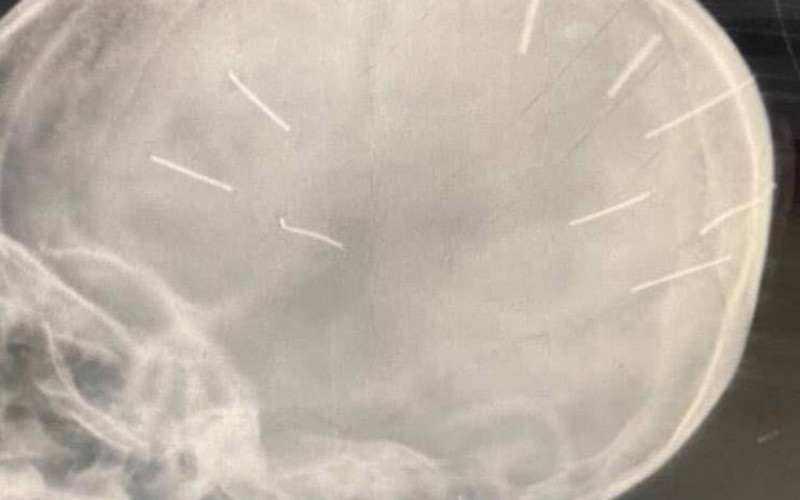

Hình ảnh phim chụp X-quang phát hiện trong hộp sọ cháu bé có nhiều dị vật giống đinh.

Trước đó, thông tin từ phía Bệnh viện đa khoa huyện Thạch Thất được biết, chiều 17/1, bệnh viện tiếp nhận một bé gái 3 tuổi (trú tại xã Canh Nậu, huyện Thạch Thất) nhập viện trong tình trạng hôn mê. Sau khi chụp X-quang phát hiện trên hộp sọ cháu bé có 9 dị vật lạ giống đinh.